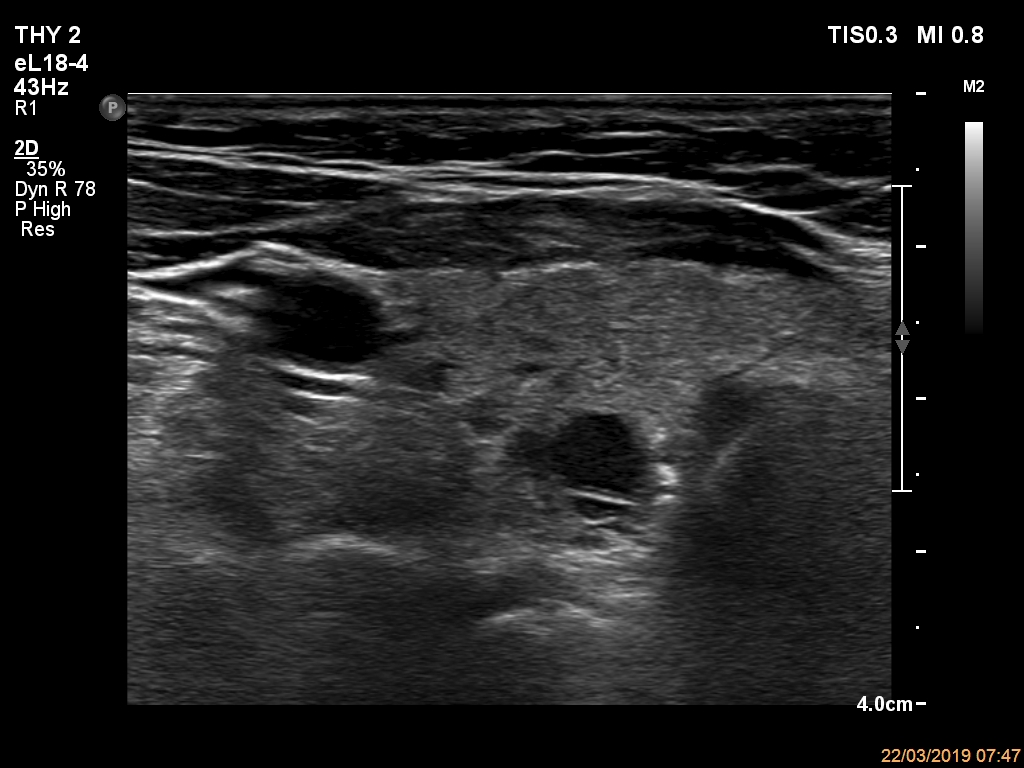

Ultrasonography. The thyroid was echonormal and had multiple nodules. The only lesion of a possible oncological importance was in the left lobe. It was hypoechoic. The dimensions were 16x14x23 mm (width, depth, length, respectively). The lower border presented an undulation which was caused by another, hyperechoic nodule. The nodule presented a predominant perinodular blood flow and had an average rigidity on elastography.

The nodule in the left lobe illustrates non-pathological form of lobulated margins.